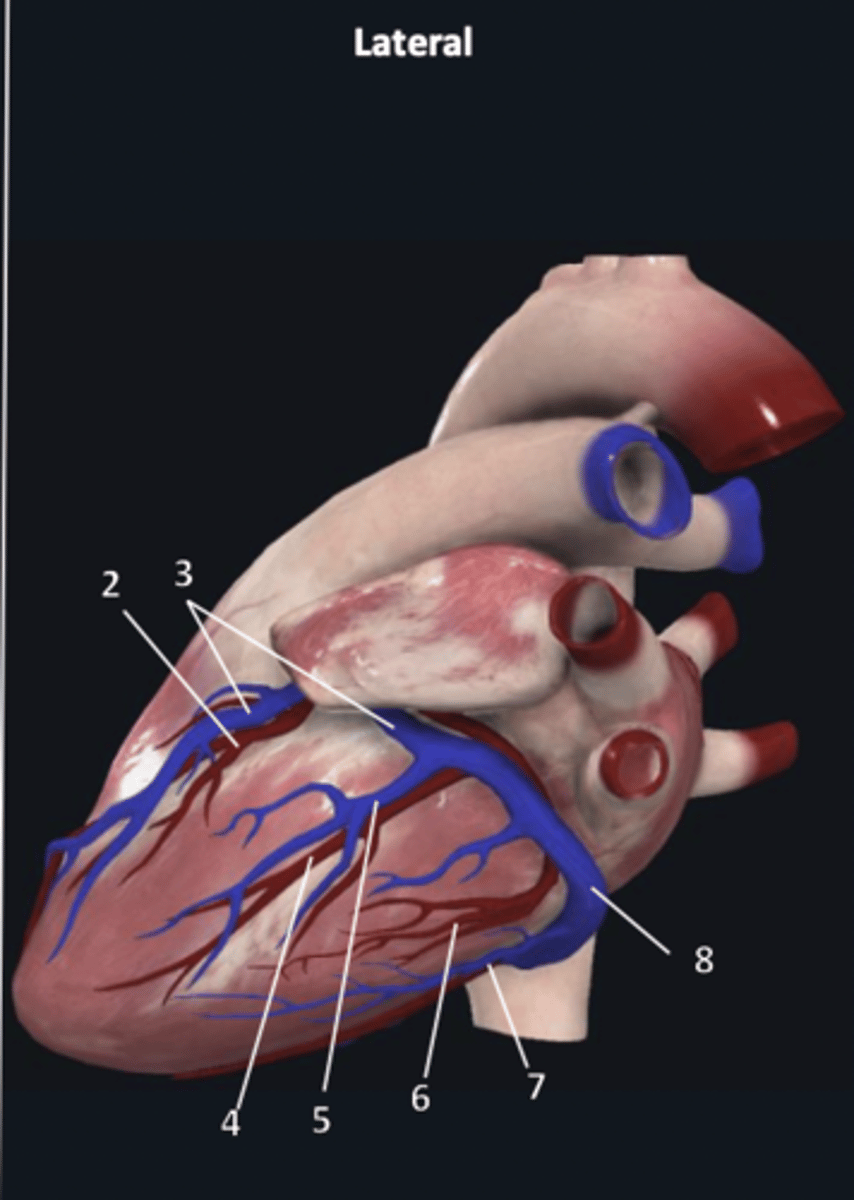

right coronary artery

1

anterior interventricular artery

2 (red)

great cardiac vein

3 (blue)

anterior interventricular artery

2 (red)

great cardiac vein

3 (blue)

left marginal artery

4

left marginal vein

5

posterior left ventricular artery

6

posterior vein of left ventricle

7

coronary sinus

8